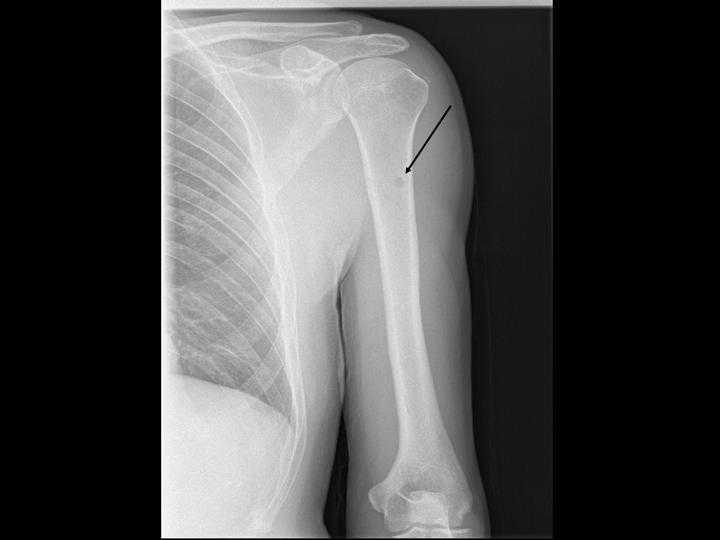

Una serie ósea completa evidenció múltiples lesiones líticas en huesos largos (figura 1) y cráneo (figura 2), sugestivas de mieloma múltiple.

Las lesiones líticas son uno de los criterios diagnósticos y se desarrollan en casi el 80 % de los pacientes. El 58 % de los pacientes refiere dolores óseos en el momento del diagnóstico. La serie ósea todavía es el método recomendado para el diagnóstico de estas, pero solo identifica aquellas con avanzado grado de destrucción ósea, que afectan a un mínimo del 30 % del hueso trabecular, pudiendo llegar a afectar hasta al 50-75 %. La resonancia magnética se recomienda si la serie ósea es normal o si se sospecha un plasmocitoma solitario del hueso3.

Figura 1. Lesión lítica en el brazo izquierdo